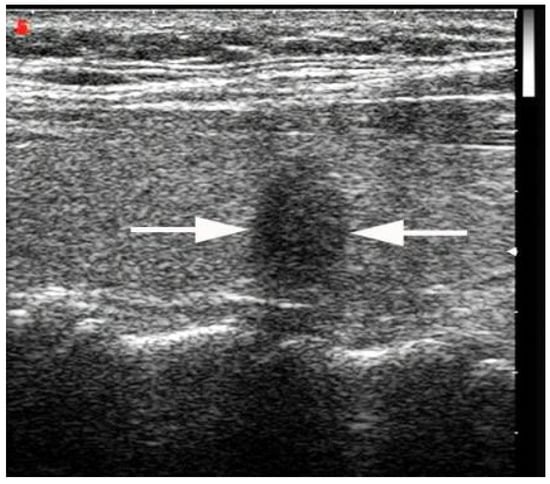

- Chen, S.-P.; Hu, Y.-P.; Chen, B. Taller-Than-Wide Sign for Predicting Thyroid Microcarcinoma: Comparison and Combination of Two Ultrasonographic Planes. Ultrasound Med. Biol. 2014, 40, 2004–2011. [Google Scholar] [CrossRef]

- Kwak, J.Y.; Kim, E.-K.; Youk, J.H.; Kim, M.J.; Son, E.J.; Choi, S.H.; Oh, K.K. Extrathyroid Extension of Well-Differentiated Papillary Thyroid Microcarcinoma on US. Thyroid 2008, 18, 609–614. [Google Scholar] [CrossRef]

- Moon, S.J.; Kim, D.W.; Kim, S.J.; Ha, T.K.; Park, H.K.; Jung, S.J. Ultrasound assessment of degrees of extrathyroidal extension in papillary thyroid microcarcinoma. Endocr Pract. 2014, 20, 1037–1043. [Google Scholar] [CrossRef]

- Chung, S.R.; Baek, J.H.; Choi, Y.J.; Sung, T.Y.; Song, D.E.; Kim, T.Y.; Lee, J.H. Sonographic Assessment of the Extent of Extrathyroidal Extension in Thyroid Cancer. Korean J. Radiol. 2020, 21, 1187–1195. [Google Scholar] [CrossRef]

- Ramundo, V.; Di Gioia, C.R.T.; Falcone, R.; Lamartina, L.; Biffoni, M.; Giacomelli, L.; Filetti, S.; Durante, C.; Grani, G. Diagnostic Performance of Neck Ultrasonography in the Preoperative Evaluation for Extrathyroidal Extension of Suspicious Thyroid Nodules. World J. Surg. 2020, 44, 2669–2674. [Google Scholar] [CrossRef] [PubMed]

- Jeong, S.Y.; Chung, S.R.; Baek, J.H.; Choi, Y.J.; Sung, T.-Y.; Song, D.E.; Kim, T.Y. Sonographic assessment of minor extrathyroidal extension of papillary thyroid micro-carcinoma involving the posterior thyroid capsule. Eur. Radiol. 2022, 32, 6090–6096. [Google Scholar] [CrossRef] [PubMed]